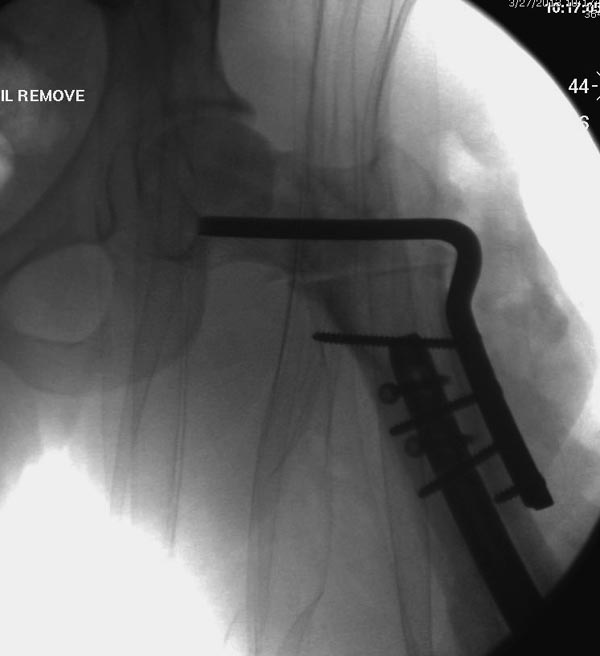

Здесь выставлен ренгенограммы больного, ему 21, травму получил в результате высокоскоростной погони на украденной машине, которая закончилась смертью трех остальных “боевых комрадов”. Начатую коллегой открытую операцию на шейке пришлось закончить мне, установкой винтов и ретроградной фиксацией бедра. Выписка в обычное сроки и наблюдался амбулаторно. Каждый раз напоминали о возможности осложнений ввиде несращения! По истечению 4 месяцев появились признаки варусной деформации. На СТ срезах несращение шейки и бедра. Риминг, замена на более толстый гвоздь и вальгусная остеотомия.